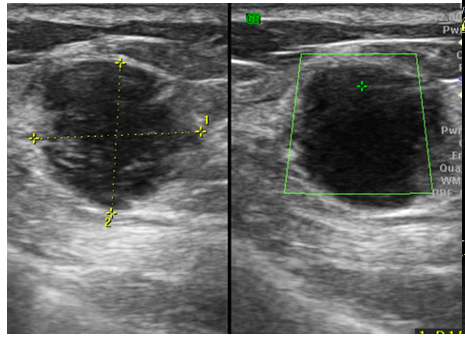

44 year old lady presenting with painless lump in right breast since 1...

Read More